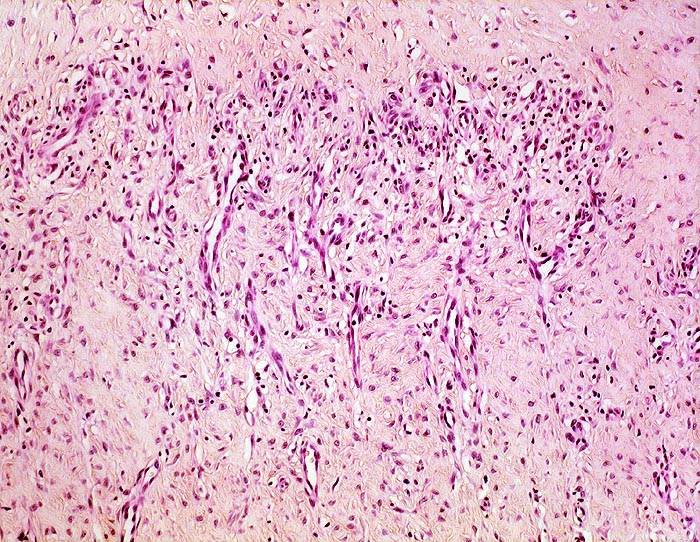

Chronische Bursitis

Als Folge frischer Schädigungen findet sich der inneren Oberfläche aufgelagertes Fibrin, das von Granulationsgewebe organisiert wird. Die operativ entfernten Bursen zeigen meist Veränderungen einer chronischen Bursopathie.

• Eröffnete Bursa mit plumpen Zotten mit kompakten Auflagerungen von hypereosinophilem Fibrin.

• Innenauskleidung durch eine Schicht flacher Synoviozyten.

• Daran angrenzend gefässreiches Granulationsgewebe mit lumennahen Erythrozytenextravasaten und Narbengewebe.

• Weiter aussen folgt Fettgewebe mit breiten Bindegewebssepten.